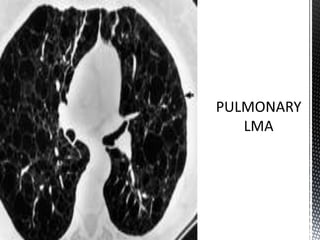

*CT scan and high-resolution CT scan findings include

the following:

 Diffuse thin-walled cysts - The defining appearance in LAM